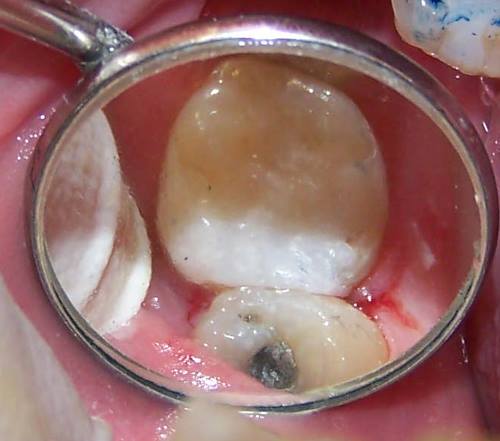

לבנות מבנים גשרים כתרים שתלים גלריה   איך עושים סתימה לבנה ?        שן

עליונה עם סתימה כסף שבור  עששת

עמוקה   גילוי

עששת

לאחר                                                                                             הוצאת

סתימת

הכסף